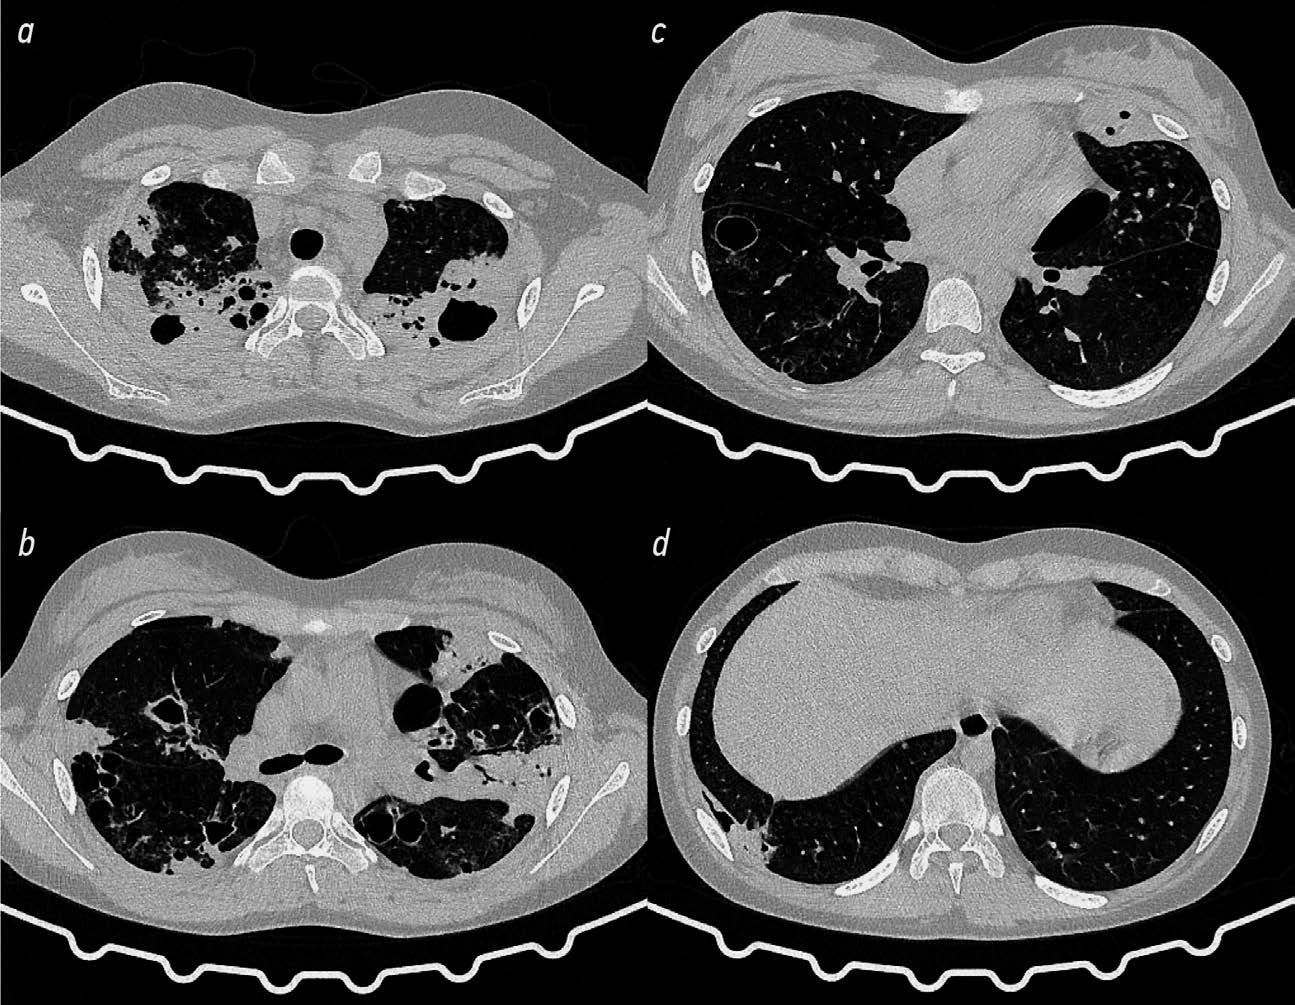

КТ ОГК через 3 мес. после операции: состояние после верхней лобэктомии с резекцией SVI, частей SV и SVIII правого лёгкого; слабовыраженная двусторонняя инфильтрация; инфильтративно-ателектатическое уплотнение оставшихся частей SV и SVIII правого лёгкого; ФКТ SI–II, VI левого лёгкого с наличием гигантской каверны; положительная динамика в виде закрытия одной из полостей в SVI левого лёгкого (рис. 5).

Рис. 5. Компьютерная томография органов грудной клетки через 3 мес. после комбинированной резекции правого лёгкого: фиброзно- кавернозный туберкулёз SI, II, VI левого лёгкого с гигантской каверной (описание в тексте).

Fig. 5. Computed tomography of the chest organs 3 months after combined resection of the right lung: fibrotic cavernous tuberculosis SI, II, VI of the left lung with a giant cavern (description in text).